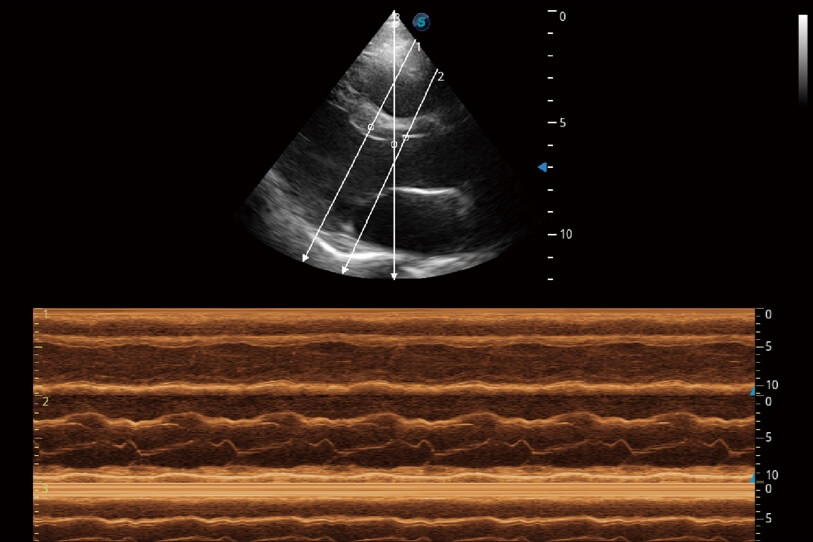

通過360度任意調(diào)節(jié)3條M型取樣線,在同一心動(dòng)周期上觀察心臟不同位置的運(yùn)動(dòng)曲線,得到準(zhǔn)確的心功能測(cè)量數(shù)據(jù),有效評(píng)估心肌運(yùn)動(dòng)及左心室功能。